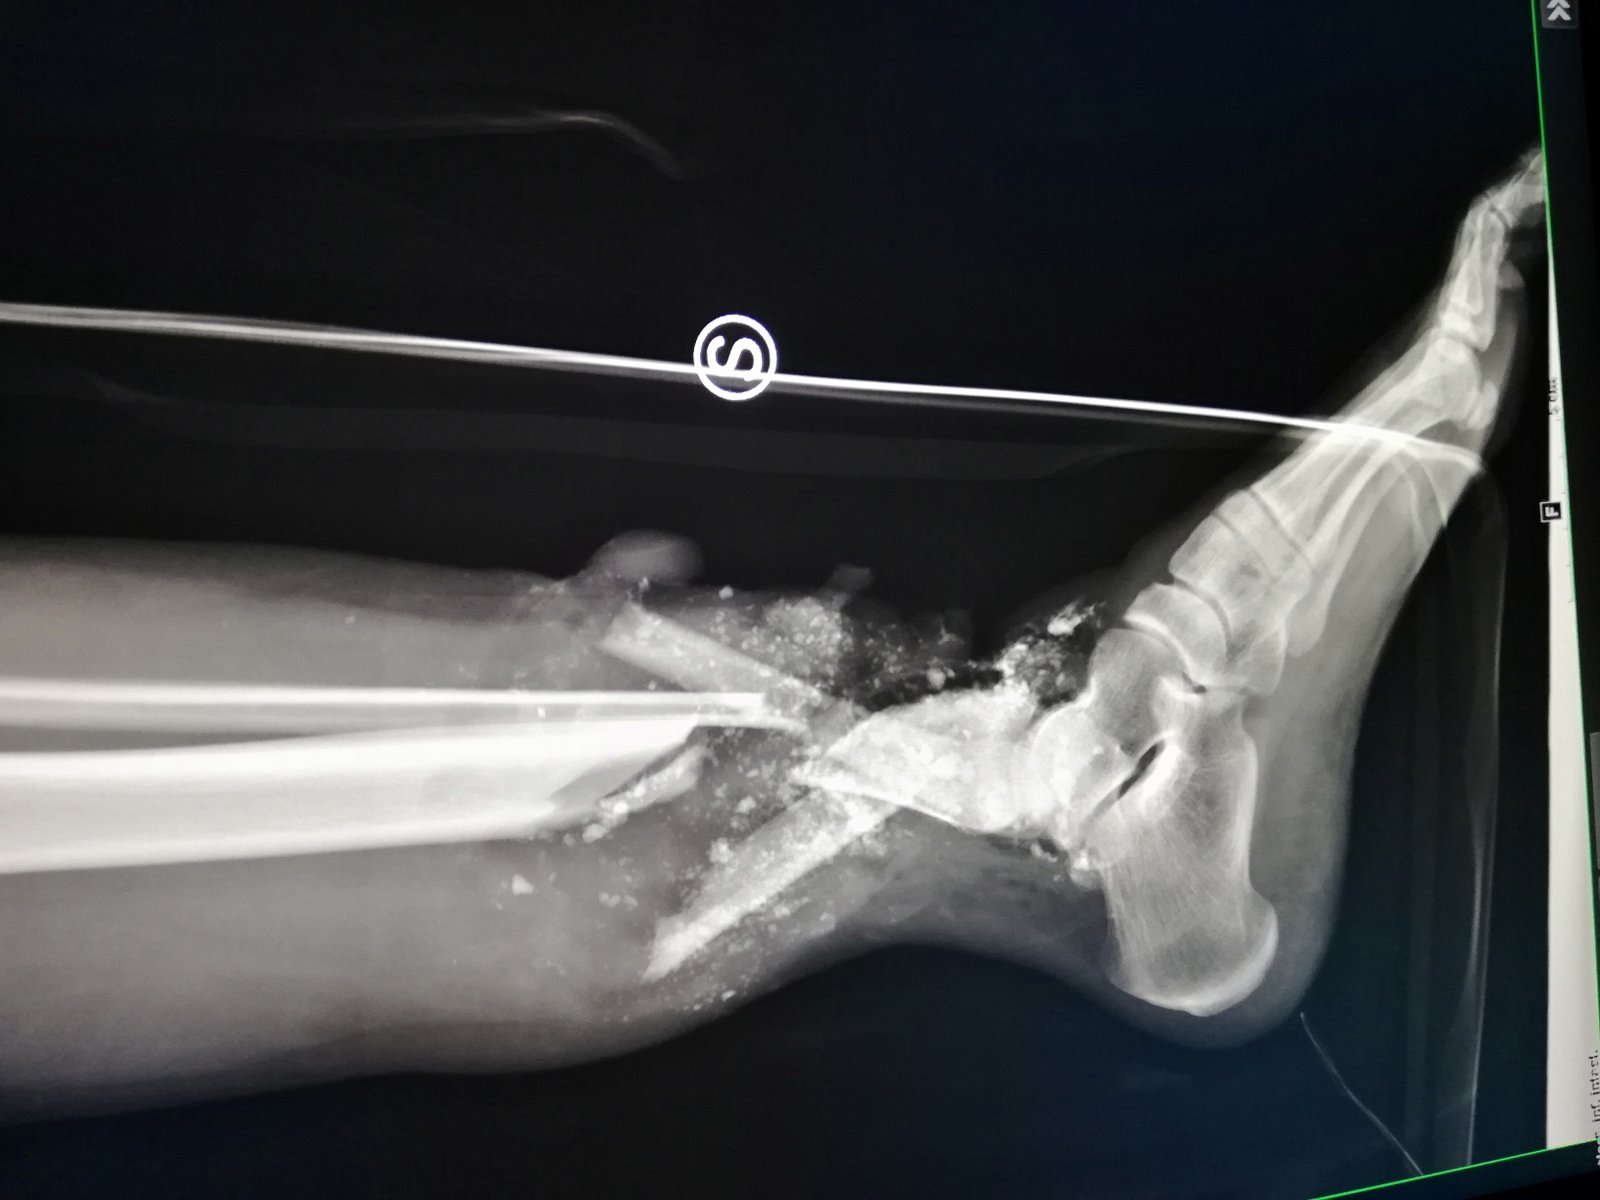

Esposizioni ossee, fratture comminute e contaminate, alterazioni della vascolazrizzazione, deficit cutanei, tendinei e muscolari sono tutte situazioni che la chirurgia ricostruttiva può risolvere nella maggior parte dei casi.

Un particolare elemento critico è la continuità nervosa, in particolare del nervo tibiale posteriore (o a livello della coscia del nervo sciatico). Il motivo risiede nel fatto che la sensibilità a livello dell'arto inferiore (e quindi della regione plantare) è di cruciale importanza per la deambulazione, e la ripresa funzionale di un nervo ricostruito (soprattutto a livello dell'arto inferiore) è spesso scarsa, rischiando pertanto di creare un arto funzionalmente non valido.